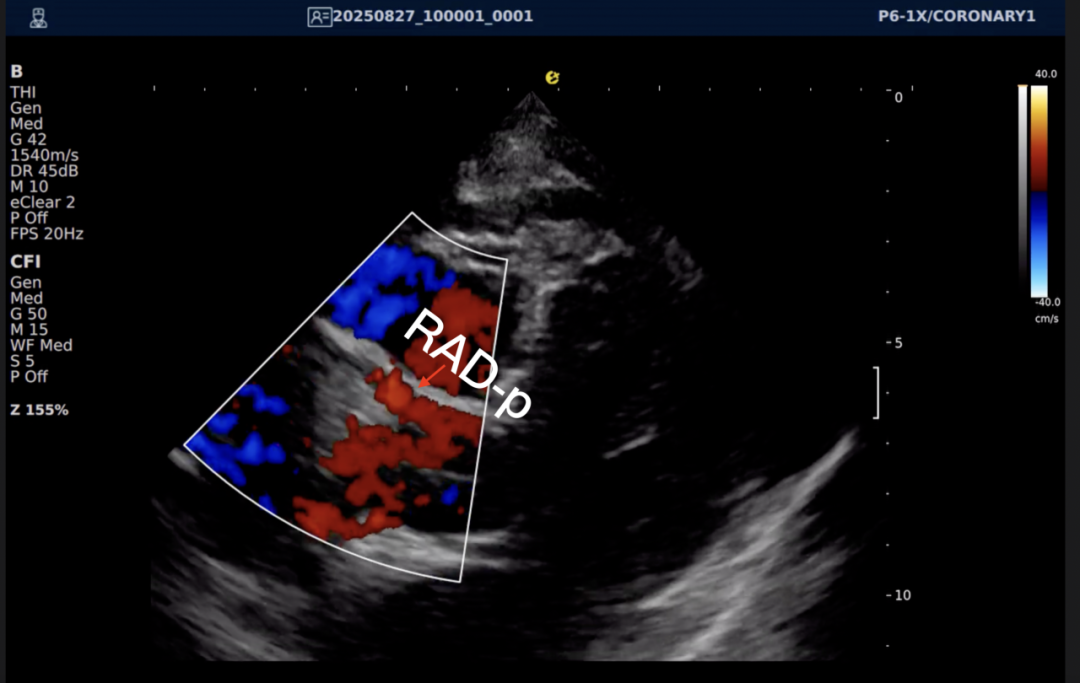

以下为逸超医疗(ESI)设备采集的冠脉图像,清晰展示了其在二维成像、彩色多普勒及频谱多普勒方面的表现:

左右滑动查看更多

心脏冠脉超声